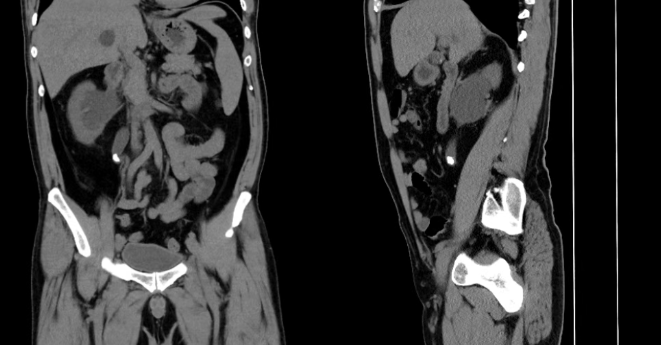

入院完善全腹CT检查提示:右侧输尿管上段结石位置无变化、右肾积水较前明显加重,影像学提示:输尿管走行迂曲、管腔狭窄,结石已长期嵌顿、包裹与管壁粘连紧密,属于复杂性输尿管结石,常规碎石难度大、风险高,极易出现结石漂移、输尿管损伤。